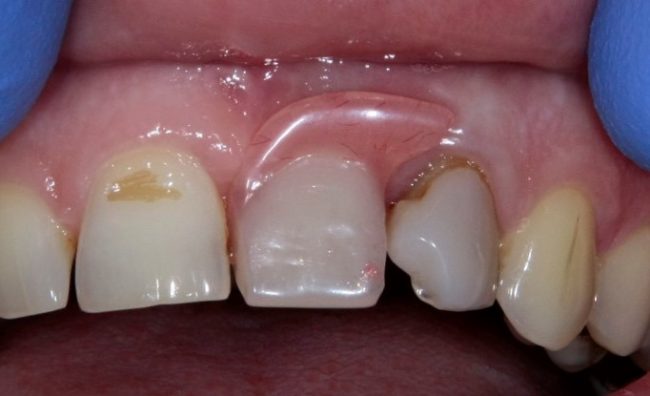

Но это еще не самое веселое. Допустим, мы решили проблему соединения «имплант-абатмент», у нас нет проблем с люфтами, а сам имплантат настолько хорошо интегрировался, что способен любую нагрузку в любом направлении. Возникает другая проблема — размер супраструктуры и соответствие ее нормальной биологической длине коронки зуба:

На фотографии выше, коронки опираются на обычные импланты, но даже в этом случае увеличение высоты супраструктуры усложняет гигиену и требует более пристального дальнейшего наблюдения. С ультракороткими имплантами, если честно, всё еще хуже.

Как будет выглядеть такая конструкция? Какой длины будут коронки? Возможно, на эстетику даже можно забить, ведь для некоторых людей красота зубов в боковом сегменте челюсти за пределами эстетически значимой зоны не так важна, но… как быть с уходом за протетической конструкцией и ежедневной гигиеной? Ведь, чем больше по размеру протез, тем сложнее за ним ухаживать. Тем больше мест, где может остаться зубной налет, а это, как вы понимаете, может привести к очень неприятным последствиям — периимплантиту, что для ультракоротких имплантов очень критично. А застревание пищи между протезом и десной? Можно ли назвать это «повышением качества жизни пациента»? Вряд ли.